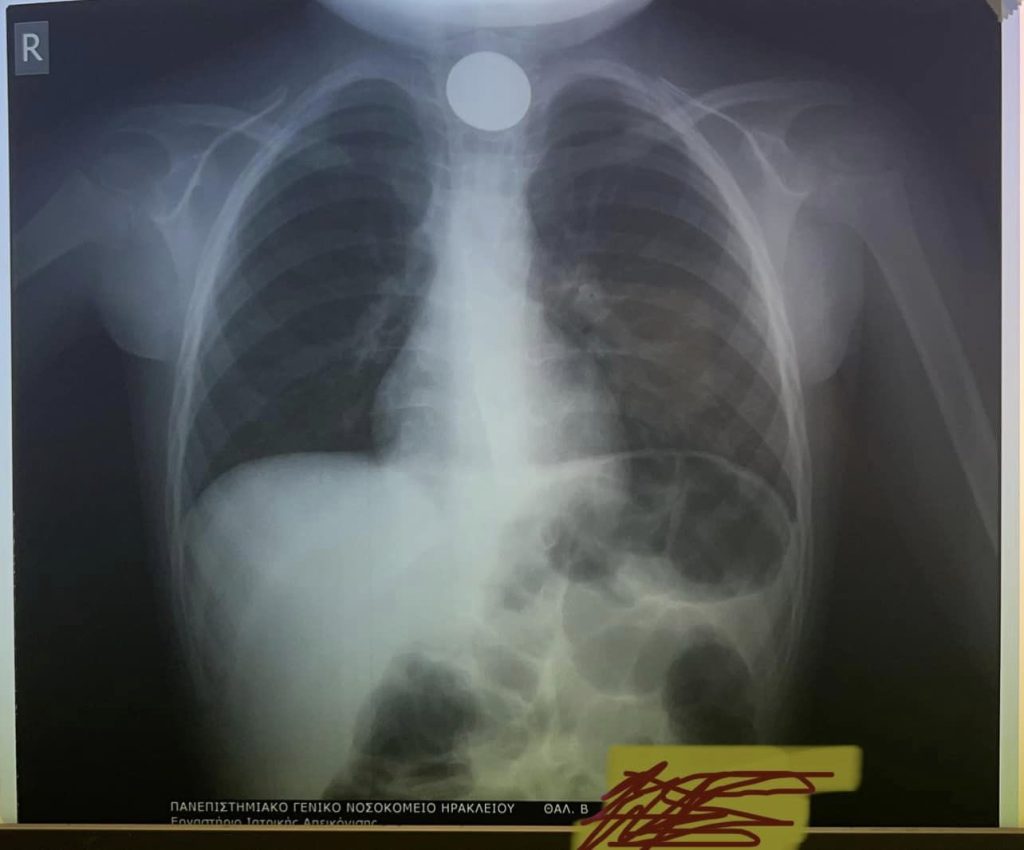

Στην Ωττορινολαρυγγολογική Κλινική του ΠΑΓΝΗ διακομίσθηκε ένα 4χρονο αγοράκι που είχε καταπιεί ένα κέρμα. Το νόμισμα είχε σφηνωθεί στον λαιμό του μικρού παιδιού όπως διαπιστώθηκε μετά την ακτινογραφία στην οποία υποβλήθηκε, όπως έγραψε το neakriti.gr.